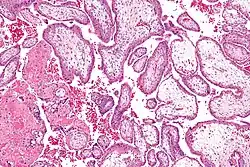

Chorionvilli (H&E-kleuring) -

Chorionvilli zeer sterke vergroting. (H&E-kleuring) -